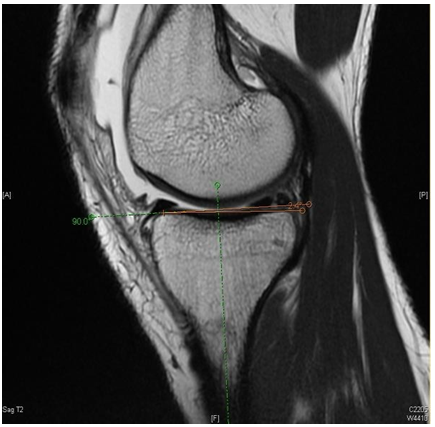

A sagittal T2 MRI cut in the middle of the medial tibial compartment was chosen for all patients to measure the PTS angle. First, the PTS angle was measured by drawing an intramedullary line parallel to the volar cortex of the tibia, and a perpendicular line is drawn over our first line. Then, a third line to be drawn between the highest bony tips of the anterior and posterior aspect of the tibial plateau. Finally, the second and third line is measured angle delineated the posterior tibial slope (Figure 1 & 2).

Figure 2 Technique of measuring the PTS.